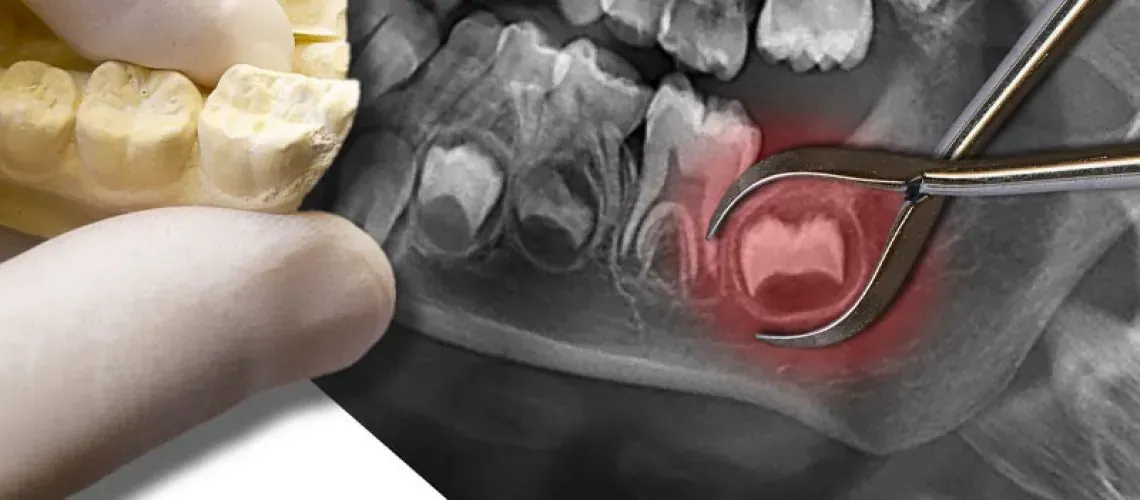

Impacted wisdom teeth can cause pain, infection, and damage to the surrounding teeth. When impacted wisdom teeth cause problems, a skilled doctor may treat them with a wisdom tooth removal in Williamsville, NY. Continue reading to learn more about the problems problematic wisdom teeth can cause, and how they can be removed.

When people have impacted wisdom teeth, they should go to an experienced doctor for a wisdom tooth removal in Williamsville, NY. Before the procedure even begins, the doctor can numb the area and remove the problematic wisdom tooth with special instruments.